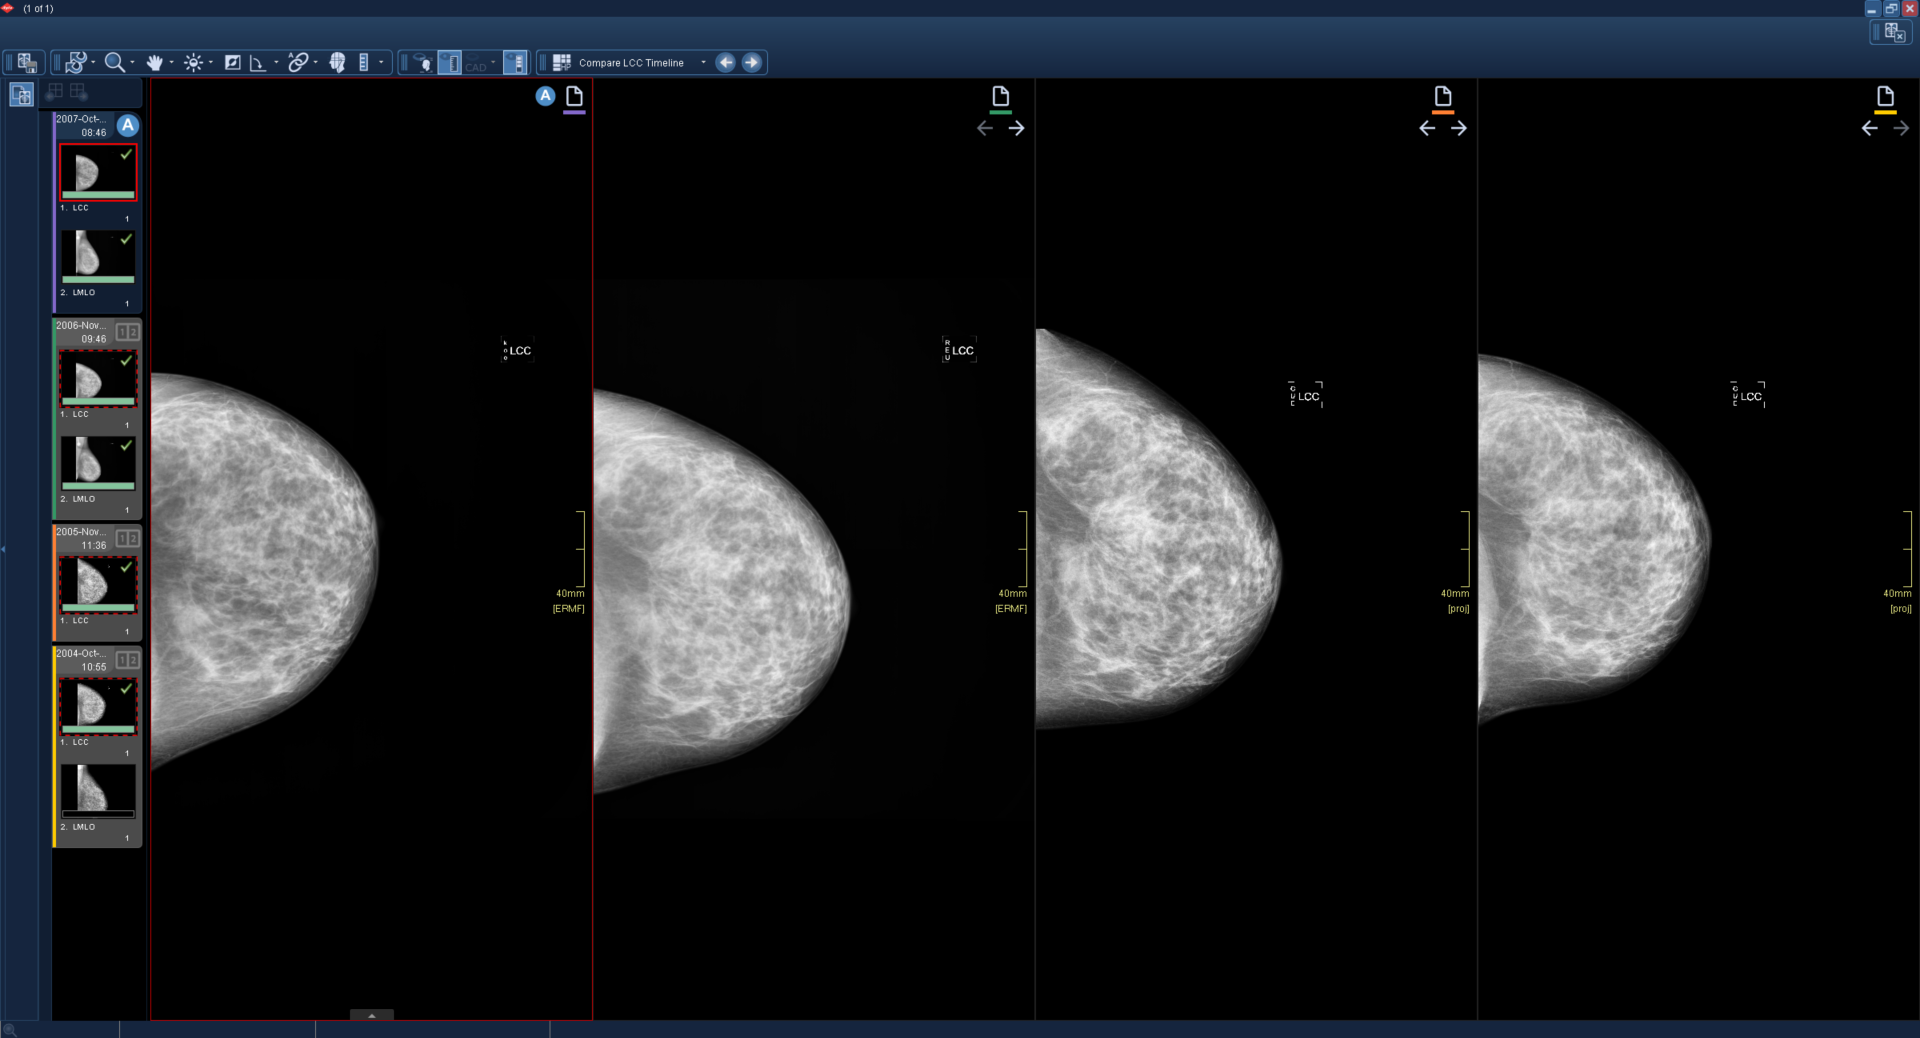

1

Μια ενεργή εξέταση με τρεις συγκριτικές εξετάσεις φορτώνεται και εμφανίζεται χρησιμοποιώντας το πρωτόκολλο ανάρτησης Compare LCC Timeline.

Χρησιμοποιώντας τη συντόμευση επόμενης συγκριτικής εξέτασης, όλα τα παράθυρα μετακινούνται στην επόμενη συγκριτική εξέταση. Όταν δεν υπάρχουν διαθέσιμες περαιτέρω συγκριτικές εξετάσεις, το παράθυρο είναι μαύρο.

Χρησιμοποιώντας ξανά τη συντόμευση επόμενης συγκριτικής εξέτασης, η τελευταία συγκριτική εξέταση μετακινείται δίπλα στο ενεργό παράθυρο. Όλα τα άλλα παράθυρα σύγκρισης παραμένουν μαύρα.

Η έγχρωμη γραμμή κάτω από το εικονίδιο εξέτασης παραμένει συγχρονισμένη με την πλαϊνή γραμμή κλινικών στοιχείων.